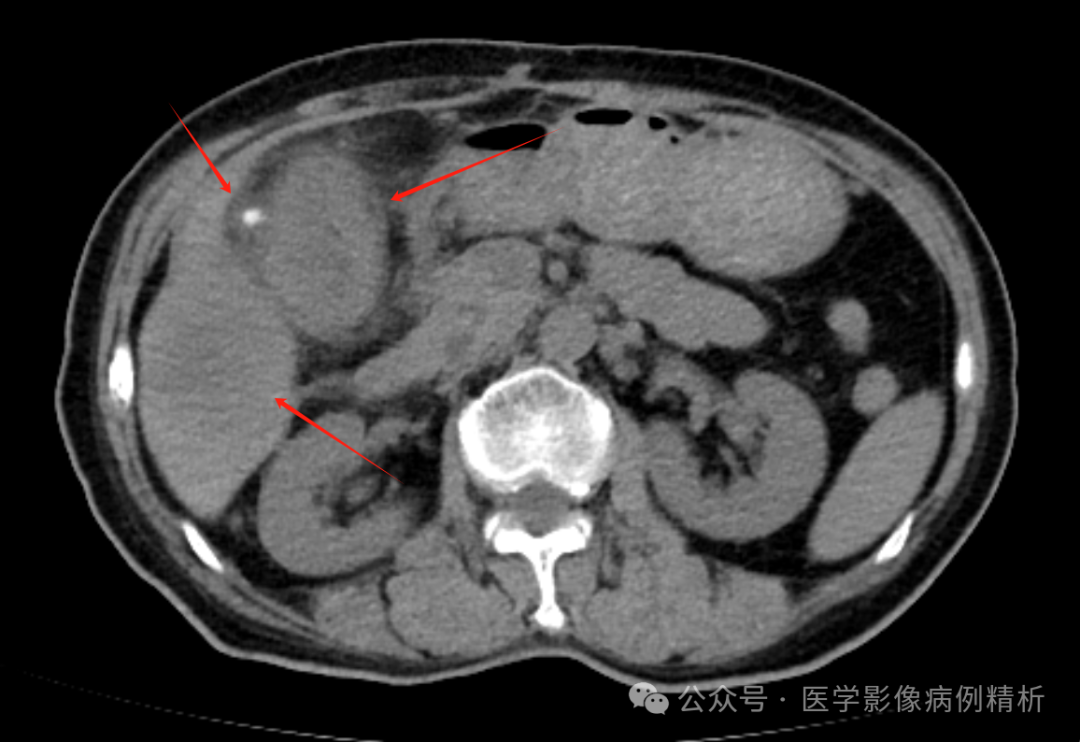

结肠癌并肝转移,胆囊结石CT影像分析

本例不给病史,直接考验AI诊断的能力;后期补充病史,看自我修正的能力。最后给出报告结论。

直接给出CT图像并没有给出病史时,三种AI工具答案完全错误;

给出结肠癌提示后,三种AI工具答案完全给出结肠癌、区域性淋巴结转移、可能肝转移报告结论,其中kimi很惊艳的给出结肠肝曲的解剖部位提示,但是三种工具都没有给出胆囊结石的结论,明晃晃的一个图像表现。

对于结肠癌的CT图片,没有给出病史的时候,三种工具诊断完全错误;给出病史,都提及了结肠癌、肝转移瘤、区域性淋巴结转移,但是kimi给出了结肠肝曲的具体解剖部位,相对略高一筹。但是都漏了明晃晃的胆囊结石,这个错误,无比巨大。